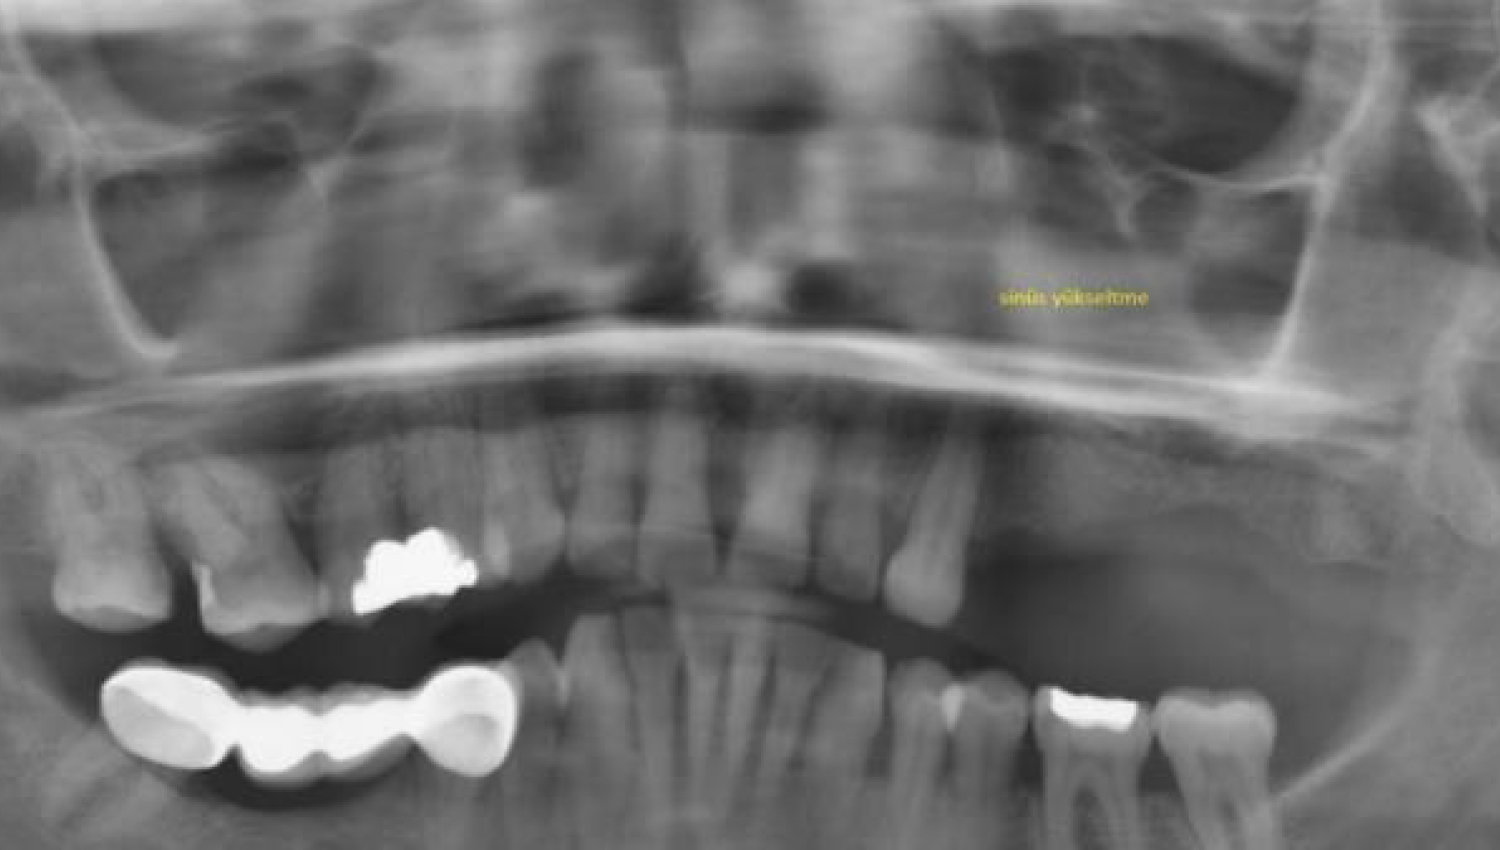

1.Initial radiological view.

2.Crestal sinus lift with modificated technique using Powerbone Dental Putty.